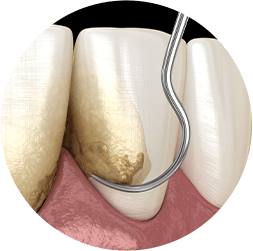

scaling and Root Planing

Gum disease can be cause by personal habits, hormonal changes due to aging and pregnancy and in some cases, it can be the result of genetics. But usually it is the result of a build-up of plaque and tartar on the teeth above and more importantly below the gumline. Scaling and root planing can keep your smile healthy.